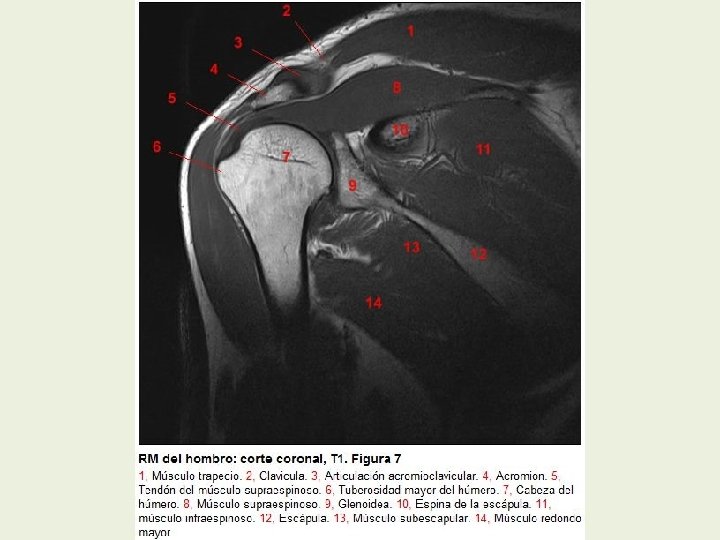

Hombro Cortes coronales RMN